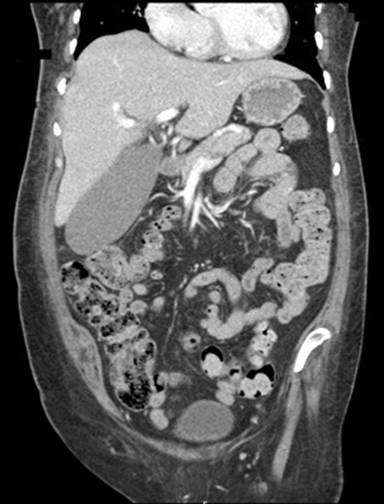

A sixty-year-old woman presented to the emergency room with a left perinephric abscess and symptomatic anemia, and history of poorly controlled type- 2 diabetes mellitus of fifteen years duration, with a glycosylated hemoglobin of 12% recorded 3 months prior to hospitalization. She came from a nursing home where her diabetes was managed with metformin and glipizide, and she had developed diabetic nephropathy (stage 2 chronic kidney disease). At the time of admission she was noted to have lost 24 pounds in weight as compared to her weight 3 months ago. She had a long-standing history of coronary artery disease and paroxysmal atrial fibrillation. She also complained of lower extremity weakness and initial work up suggested a polyneuropathy. Her examination was significant for conjunctival pallor and lower extremity muscle weakness. She was anemic, with hemoglobin of 6.7 g/dL. Iron studies showed low total iron binding capacity and elevated ferritin levels consistent with anemia of chronic disease. Urine analysis and urine culture studies suggested a persistent urinary tract infection and given her history of recurrent UTI’s treated with multiple courses of antibiotics, she was evaluated with a CT scan of her abdomen with intravenous contrast. The CT scan revealed a left perinephric abscess and incidentally found an enlarged gallbladder with a maximum length of 14 cm and width of 6.9 cm (Figure 2). An initial work up included a 99m Technitium hepatobiliary iminodiacetic acid (HIDA) scan, which showed no obstruction to cystic or the common bile ducts and a poor gallbladder ejection fraction of 1%, consistent with biliary dyskinesia (Figure 3). The patient’s serum albumin level had ranged between 2.5 to 3 g/dL in the last few months prior to admission but with a low serum prealbumin level of 11mg/dl, this was suggetsive of poor nutritional status. Her liver transaminases, bilirubin, and alkaline phosphatase levels were within normal limits. Based on her imaging, laboratory data, and clinical presentation she was diagnosed with HGB. The patient underwent percutaneous drainage of the perinephric abscess and was discharged back to her nursing facility to complete a prolonged course of antibiotics, and has had no acute symptoms associated with her gallbladder for the last seven months.

Figure 2. CT scan of the abdomen with intravenous contrast, coronal view, showing an enlarged gallbladder with no evidence suggestive of gall stones. |